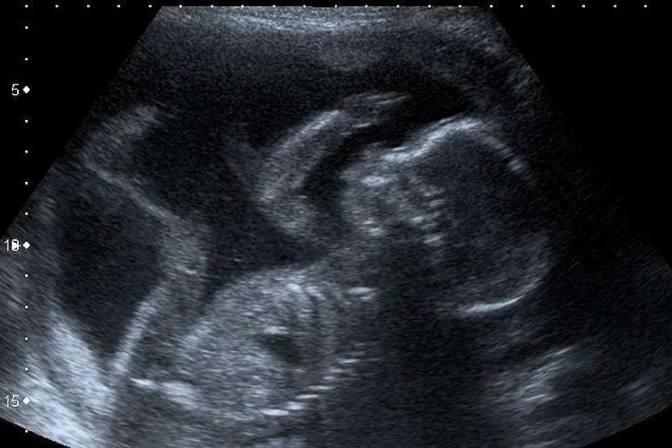

7.- Manipula los resultados de las ecografías

"Se deberá explicar a la usuaria su derecho a solicitar no ver las imágenes ni escuchar los sonidos. En caso de realizarse la ecografía, solo se compartirán con la persona la imagen o el sonido de los latidos si ella lo solicita expresamente. Si no lo hace, es de suma importancia tomar los recaudos necesarios para que aquello no suceda", describe el protocolo en la página 38.

"A su vez, si es posible, facilitar distintas áreas donde se puedan evaluar separadas aquellas mujeres que buscan una interrupción de aquellas que reciben cuidados prenatales", agrega.